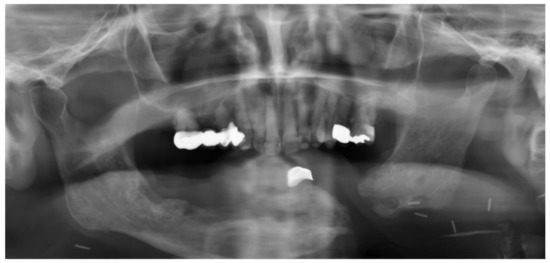

Partial mandibular resection with complete transection of the mandibular bone without reconstruction will lead to mandibular dislocation and functional asymmetry (Figure 8 and Figure 9). Radiation and scarring may even increase structural and functional asymmetry. Therefore, surgical reconstruction of the mandible is the therapy of choice whenever it is possible [123].

Figure 8.

Anteroposterior radiograph (a) and aspect of a male patient (b) suffering from oral cancer of the tongue and mandible. After tumor surgery and radiation therapy, the mandibular bones were connected by a reconstruction plate. Following local infection, reconstruction was no longer possible and, therefore, a gap between the right and left mandible remains on the patient’s left side (red dotted lines). Arrows indicate upper and lower jaw midline.

Figure 9.

Panoramic radiograph of the same patient three years later after further tooth loss.